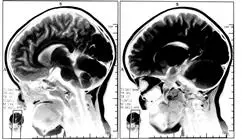

Всего за несколько лет наука и техника значительно продвинулись вперед, что привело к появлению эффективных протоколов нейрореабилитации и анализа жизненно важных функций. Кроме того, орофациальная миофункциональная терапия была распространена на пациентов с такими патологиями, как афазия и гипофония, вызванные болезнью Паркинсона. Однако быть в курсе всех этих вопросов — серьезная задача для специалистов. Во многом это связано с тем, что представленные на рынке образовательные программы недостаточно полно и современно освещают все клинические и технологические аспекты дисциплины.